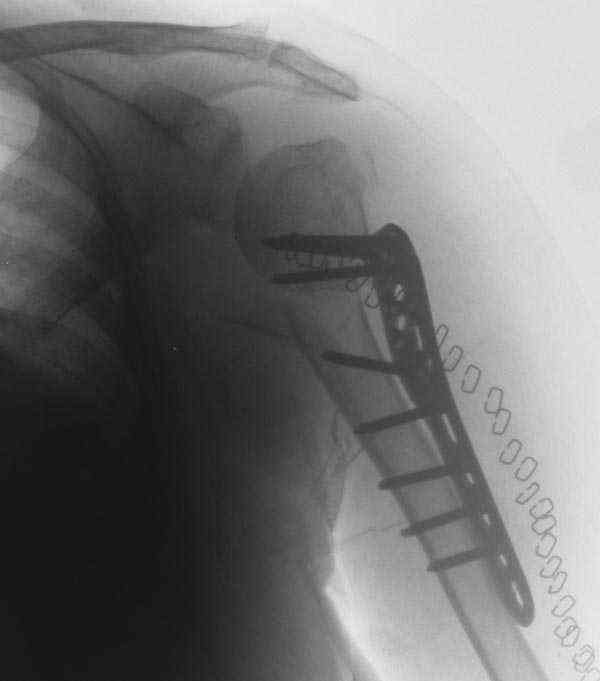

Another option could be closed nailing, see an example, the surgery was done 2 days ago. In common such surgeries are performed under regional anesthesia, not general.

I am attaching the radiographs of the mother of a doctor. She has chronic renal failure for >10 years, diabetes mellitus and coronary artery disease. Age 62. She was offered the options of non-surgical management in a sling and surgery with a locking plate. She was given Tramadol for pain relief. Five days after injury, patient requested surgery, because of pain, inability to move without pain.

The reduction is not perfect. The patient is very small made, and it was difficult to bring the plate proximally without impingement in abduction.

Pain relief after surgery was early and sustained.